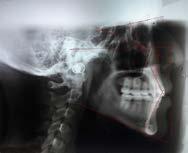

El análisis cefalométrico reveló un perfil recto, con labios superior en norma, labio inferior protruido, clase I esqueletal, incisivos en norma y crecimiento neutro (Figura 4).

Figura 4. Lateral de cráneo inicial.